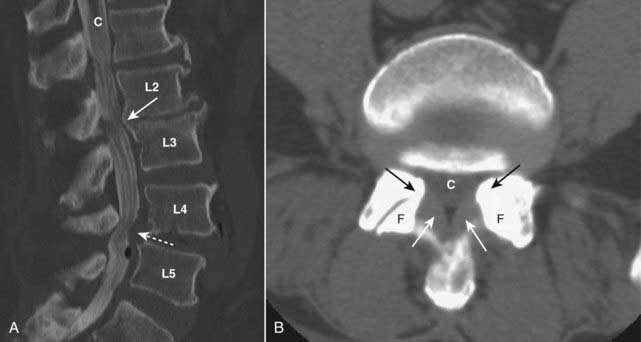

image Conventional radiographic findings may include an AP diameter of the spinal canal of 10 mm or less, facet joint arthritis, and spondylolisthesis (Fig. 24-13).

image

Figure 24-13 Spinal stenosis, CT.

A, At the level of L2-L3, there are osteophytes that narrow the canal (C) (solid white arrow). There is a protruding disk (dotted white arrow) at L4-L5 that reduces the size of the spinal canal at this level. B, The canal (C) is narrowed by thickening of the ligamenta flava (solid white arrows) and by bony overgrowth (solid black arrows) from osteoarthritis of the facet joints (F). Spinal stenosis refers to narrowing of the spinal canal or the neural foramina secondary to soft tissue or bony abnormalities.